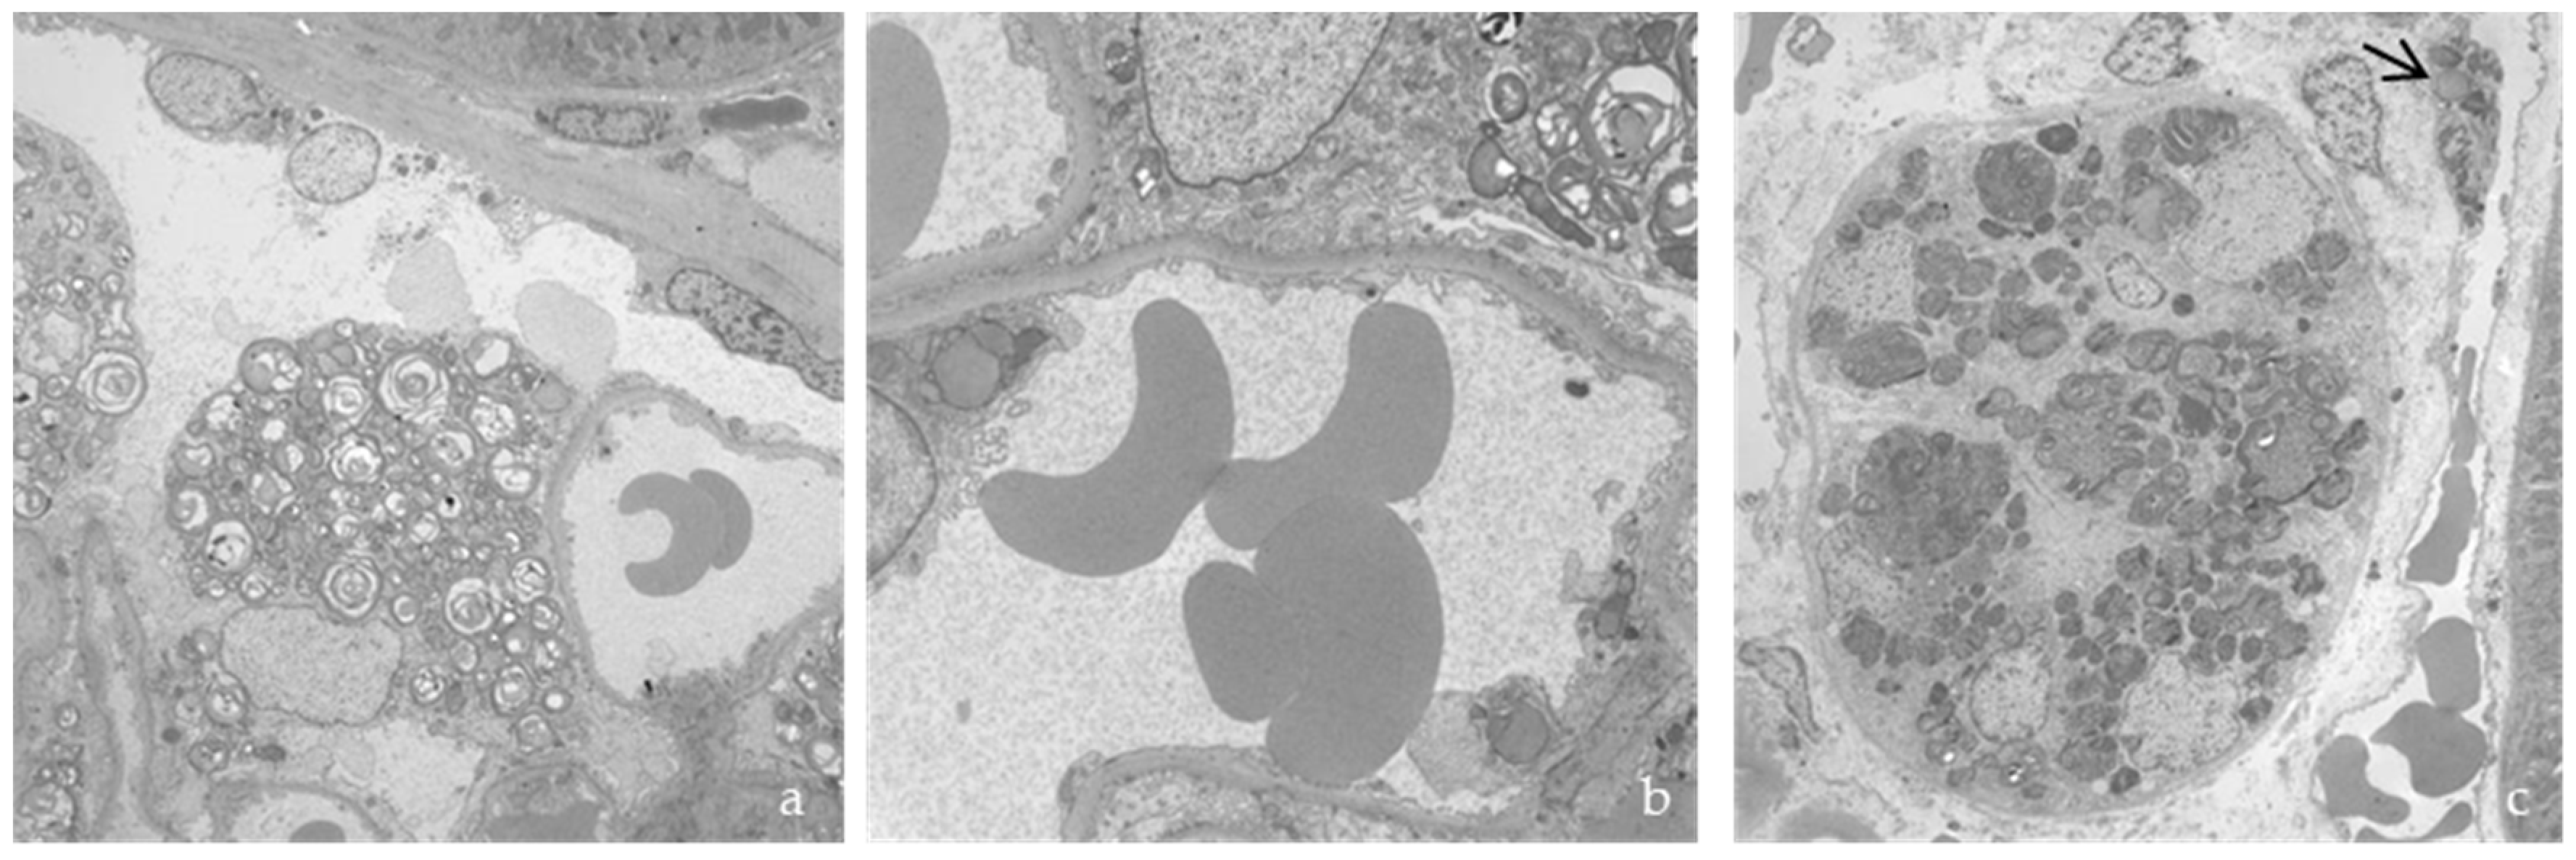

3.3. Histological and Ultrastructural Study